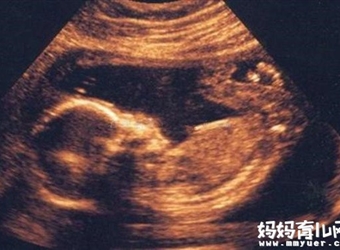

怀孕三个月即孕9-12周的时间段,这个时期很关键,胎儿的各器官的发育是在这个月里开始逐渐长成,你一定很想知道怀孕三个月胎儿是怎么慢慢长成发育的吧,怀孕三…

胎儿宝宝在母体里到底是什么状态了,他是怎么呼吸,怎么睡觉,怎么踢腿翻身的呢?下面,我们就以怀孕28周的胎儿为例,一起来探索下怀孕28周胎儿的真实图片,并…